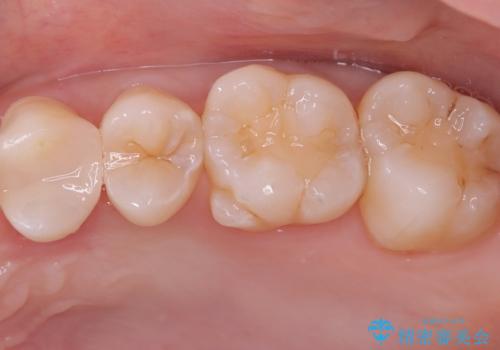

- 主訴:左上真ん中らへんの歯が欠けてしみるので治したい

審美性、適合性の良いセラミックインレーでのやり替えとなりました。

左上4近心に実質欠損を認め、遠心から咬合面にかけてはCR修復が施されていたため、MODインレー窩洞としました。

インレー接着操作時はラバーダム防湿を行っています。